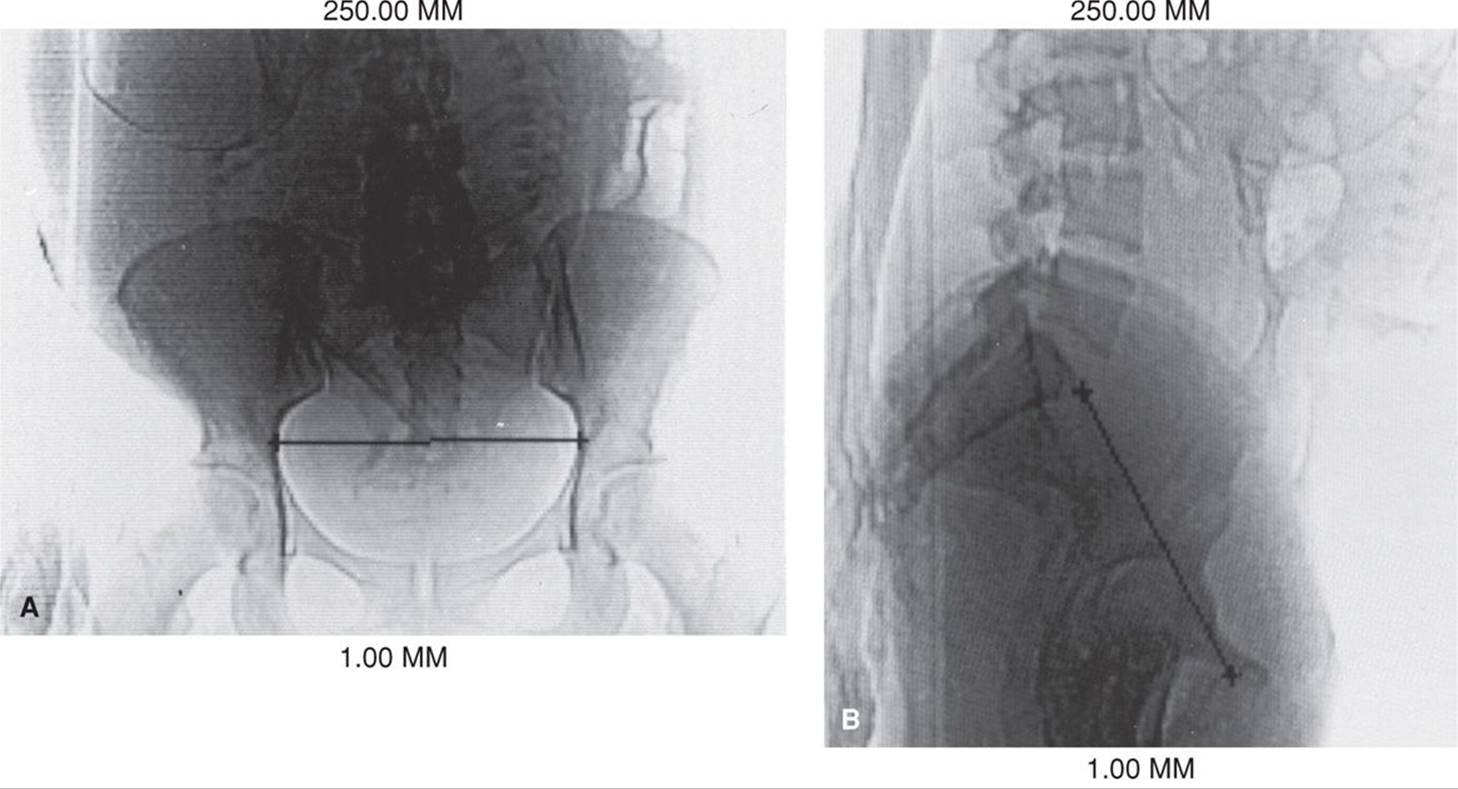

Advantages of pelvimetry with computed tomography (CT), such as that shown in Figure 23-4, compared with those of conventional x-ray pelvimetry include reduced radiation exposure, greater accuracy, and easier performance. With either method, costs are comparable, and x-ray exposure is small (Chap. 46, p. 934). Depending on the machine and technique employed, fetal doses with CT pelvimetry may range from 250 to 1500 mrad (Moore, 1989).

FIGURE 23-4 A. Anteroposterior view of a digital radiograph. Illustrated is the measurement of the transverse diameter of the pelvic inlet using an electronic cursor. The fetal body is clearly outlined. B.Lateral view of a digital radiograph. Illustrated are measurements of the anteroposterior diameters of the inlet using the electronic cursor. C. An axial computed tomographic section through the midpelvis. The level of the fovea of the femoral heads was ascertained from the anteroposterior digital radiograph because it corresponds to the level of the ischial spines. The interspinous diameter is measured using the electronic cursor. The total fetal radiation dose using these three exposures is approximately 250 mrad.